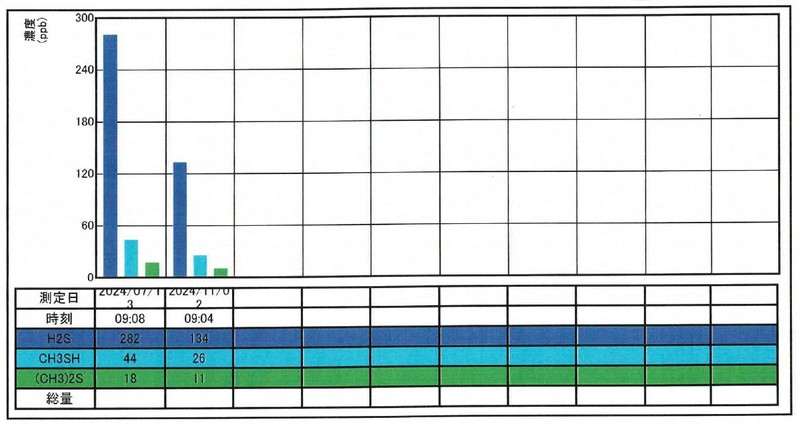

そこで、Nさんに説明をしてカウンセリング(歯周病のPCR検査や口臭検査、マイクロスコープを使用した口腔内の細かい所までの診療)に変更させていただきました。

仕事関係での疲労やストレス、喫煙習慣、自己流の歯みがきなどもヒアリングし、口腔内のトータルでの改善を目指す為に歯周病治療3週間集中プログラム(THPアドバンス)を受ける事になりました。

歯周病治療後

3週間後の再評価では、歯肉の発赤が明らかに改善し、腫れも引いてポケット深さは2~3 mmに改善。歯磨き時にも出血しなくなりました。